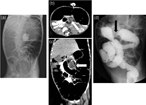

Bowel obstruction due to the migration of the deflated intragastric balloon, a rare and potentially lethal complication

Gabriel A Molina and others

Journal of Surgical Case Reports, Volume 2019, Issue 4, April 2019, rjz091, https://doi.org/10.1093/jscr/rjz091